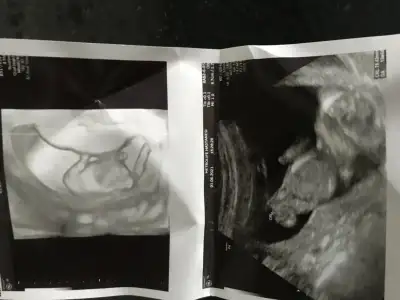

En iyi 11 12 13 haftalar olmalı şimdilik kız yönünde ama yanıltabilirIkra meyra bana da yorum yapar mısın cinsiyet için

burada 9 haftalıktı belli olur mu bilmiyorum o haftada ama bir bakabilirsen sevinirim